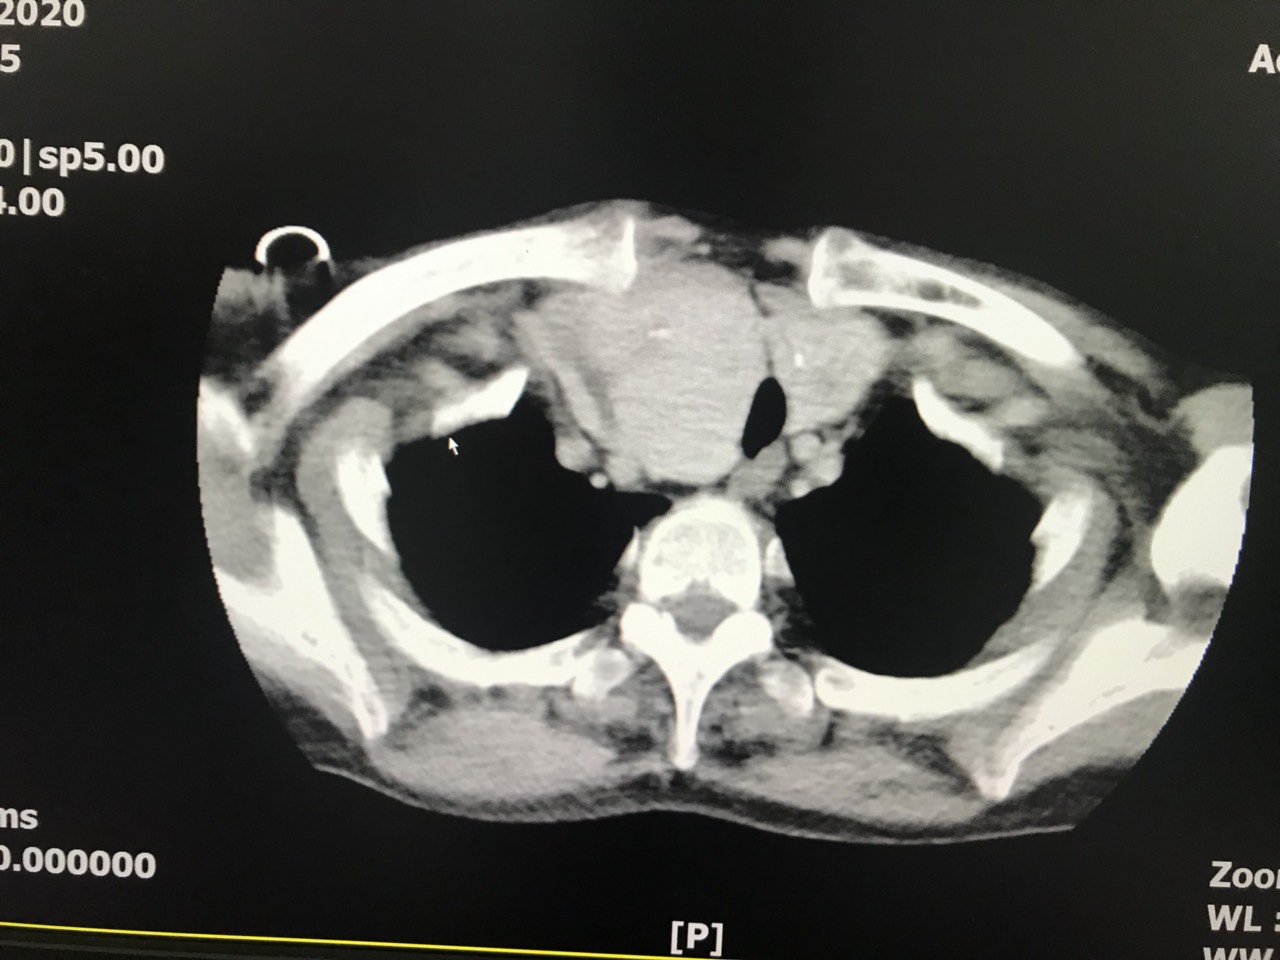

Khai thác bệnh sử, 43 năm trước bệnh nhân đã mổ dọc khí quản để chữa hóc xương (năm 13 tuổi) tạo thành một khối sẹo dính trước khí quản. Khám tuyến giáp thấy khối u cả 2 thùy độ 5 gây chèn ép khí quản, đánh giá sơ bộ, TS.BSCKII Bùi Thanh Doanh – Giám đốc Trung tâm phẫu thuật tạo hình thẩm mỹ, Bệnh viện đa khoa Quốc tế Hải Phòng xác định đây là một trường hợp khá đặc biệt, u tuyến giáp khổng lồ phát triển xuống trung thất do tổ chức sẹo dính. Eo giáp không còn do can thiệp phẫu thuật từ nhỏ và tạo sẹo dính. Bệnh nhân được chỉ định chụp cắt lớp vi tính và các xét nghiệm cơ bản, chẩn đoán: bướu giáp khổng lồ thòng xuống trung thất trên, gây chèn ép khí quản, sẹo dày dính hẹp khí quản đã có biến chứng khó thở, bệnh nhân có chỉ định phẫu thuật.

- Hình ảnh u tuyến giáp trên phim chụp X-quang